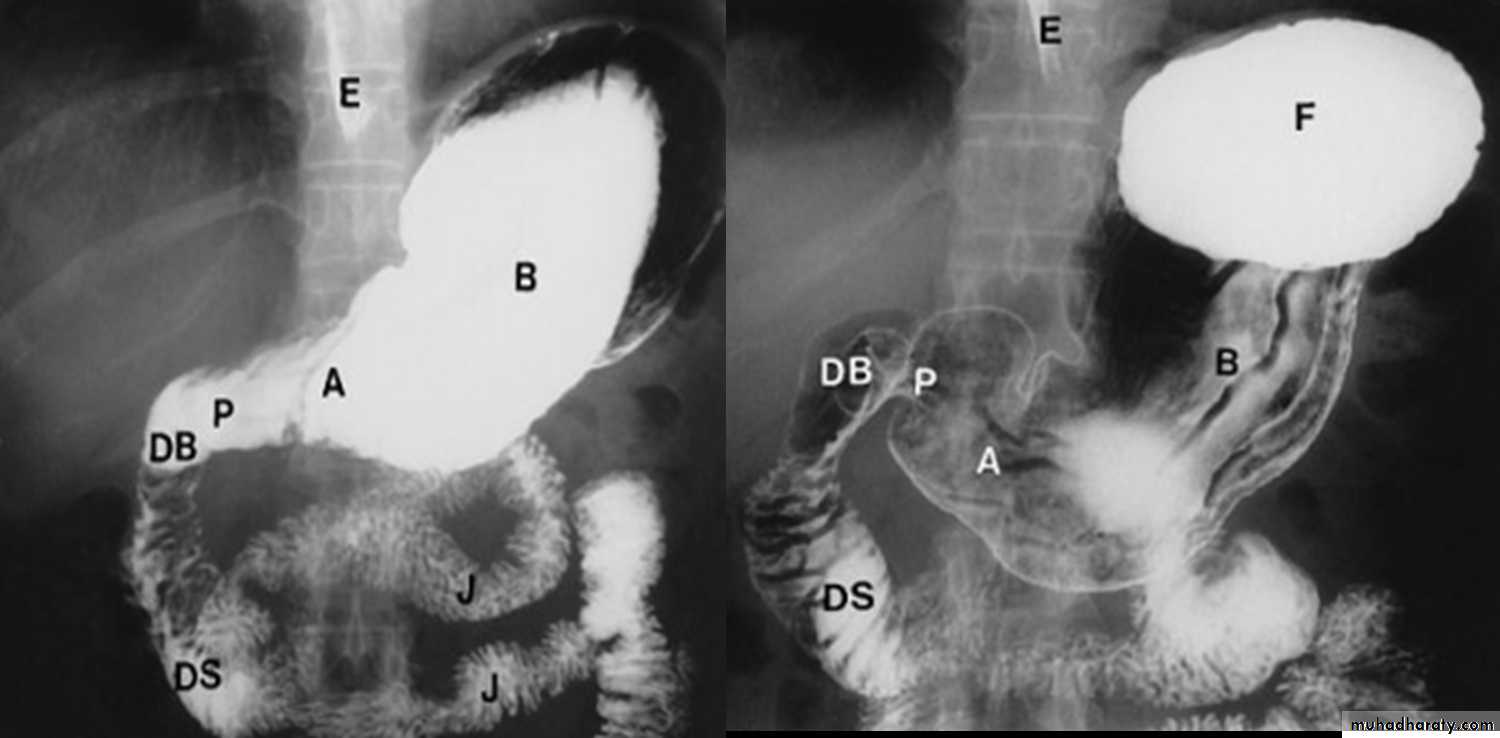

Technique of examination.Normal anatomy:

straight parallel lines.

External impression.

Barium meal

• It is contrast examination of the stomach and duodenum.

Normal appearance of the small bowel

• The normal SB occupies the central & lower abdomen.• The terminal ileum enters the medial aspect of the cecum through the ileocecal valve.

• Normal mucosa exhibit a feathery appearance [Valvulae conniventes].

• The diameter of SB loop should not exceeds 3 cm .

• Jejunum is wider than the ileum.

• Valvulae conniventes is conspicuous at jejunum more than the ileum.